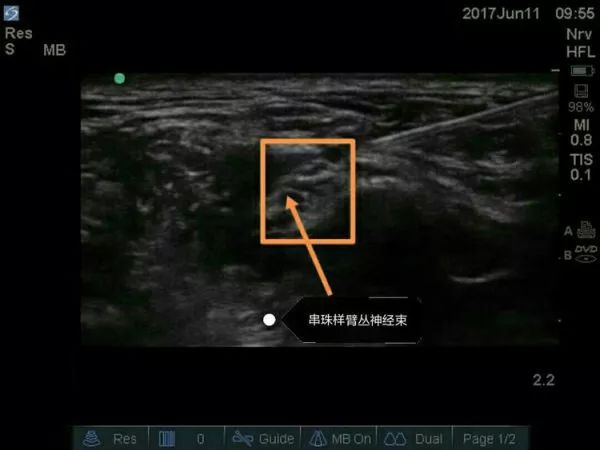

超声引导穿刺针逐渐接触臂丛神经图像